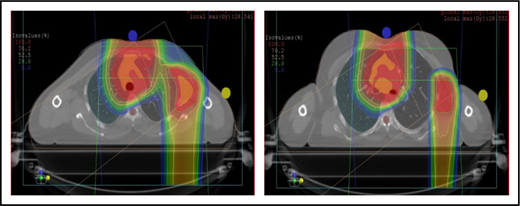

When hilar disease needs to be covered, the dose to the breasts can increase, and avoiding the breasts becomes difficult with either modality (proton or photon). The choice of treatment modality for such cases must consider the doses received by other critical structures, such as the heart and lungs, especially in previously and heavily treated patients. However, in considering how to best limit the volumes exposed to radiation, avoiding “low-dose baths” is equally important (ie, irradiation of large volumes with low doses), regardless of which modality is used (Figure 3B).

Consideration of lung dose

With the advent of CT-based planning for mediastinal lymphoma, the dose to the lungs can now be correlated with the risk for pneumonitis. Restrictions on lung dose are encouraged to be V5 < 55%, mean lung dose < 13.5 Gy, and V30 < 20%. These values are more attainable with the use of DIBH.38 Although a mean lung dose of 13.5 Gy has been associated with a lower risk for pneumonitis, it is advisable to aim for a lower dose, which is quite often attainable when strict constraints are used. For example, when IMRT is used, it is important to limit the beams to some variation of anteroposterior beams, avoiding lateral beams. If avoiding the lung is the primary objective for a given patient, especially if that patient has received pulmonary-toxic chemotherapy (eg, bleomycin, busulfan, gemcitabine, brentuximab), proton therapy may better spare the lungs by reducing the low-dose bath seen with photons (Figure 3C).

Axillary involvement at presentation. (A) Axial, coronal, and sagittal views of a proton plan (left) and an IMRT plan (right) for a patient presenting with axillary involvement. Use of proton therapy in this case spares the left breast. (B) Regardless of which treatment modality is chosen, IMRT (left panel) and proton (right panel), limiting the volume exposed to radiation should include attention to avoiding a low-dose bath. (C) Limiting lung dose. If avoiding the lung is the primary objective in a given patient, especially if the patient has received pulmonary toxic chemotherapy (eg, any combination of bleomycin, busulfan, gemcitabine, brentuximab, etc.), proton therapy may better spare the lungs by reducing the low-dose bath seen with photons.